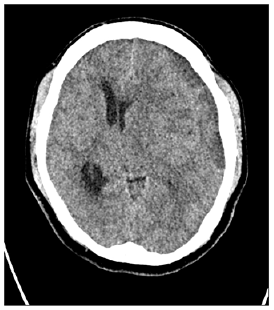

Figure 2: Postoperative follow up CT showed residual CSDH.

The age range was from 20 to 90 years with mean age of 66.5 years (Table 1). There were 122 (70.5%) males and 51 (29.5%) females. Clinically, headache was found in 83 (47.9%), hemiparesis in 141 (81.5%). There were 85 (49.1%) of patients who had the right side, 65 (37.6%) in the left side, and 23 (13.3%) in bilateral CSDH (Table 1). Radiologic follow-up showed removal of the CSDH in all cases with minimum residual in the early postoperative period and complete resolution at late follow-up. All patients were showed good clinical outcomes comparing preoperative period. Mean post-op hospital stay day was 4.5 days (range 3-8). 19 patients (10.7%) show residual CSDH cannot be drained but follow up study shows complete resolution of the CSDH. No patient required revision and no acute hematoma formation. Illustrative case (residual hematoma) A 84-year-old male patient presented with headache and right-side weakness. Brain CT showed a CSDH with midline shift. We performed burr hole drainage under local anesthesia. Postoperative patient response was good, and the patient’s symptoms was gone. However, f/up CT showed residual CSDH [9-14]. The patient symptom was good, so we wait and f/up the patient. The patient symptom was consistently good, so we did not perform further treatment and after 6months f/up CT showed total resolution of residual CSDH (Figures 1-3).